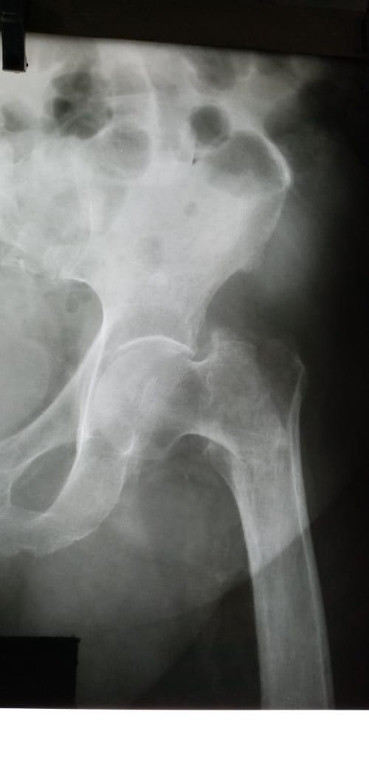

Imágenes de ortopedia y traumatología

Envíado por Dr. José Israel Flores Hernández